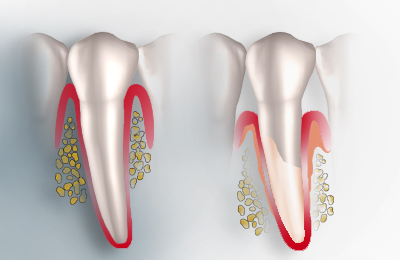

| Eine der häufigsten Erkrankungen der Bevölkerung im Bereich der Zähne ist die Parodontitis. Oft medizinisch nicht korrekt auch Parodontose genannt. Die Parodontitis ist eine durch Parodontalbakterien verursachte entzündliche Erkrankung des Zahnhalteapparates und kann unabhängig vom Alter, an nur einem oder an mehreren Zähnen gleichzeitig, unterschiedlich schnell und in verschiedenen Schweregraden auftreten. Ursache für eine Parodontitis sind Bakterien, die sich zwischen Zahn und Zahnfleisch ansammeln. Werden diese bakteriellen Beläge (Plaque) nicht durch gründliche Reinigung mit Zahnbürste und Zahnseide entfernt, bilden sie einen harten, höckerigen Belag (Zahnstein). Mit der Zeit kommt es zur Rötung, Schwellung und Blutungsneigung des Zahnfleisches. Wird dies nicht behandelt, kann diese Entzündung die Fasern, die die Zähne mit dem Kieferknochen verbinden, zerstören und im weiteren Verlauf zum Knochenabbau führen. Ohne Fasern und Knochen beginnen sich die Zähne zu lockern und gehen möglicherweise verloren. |